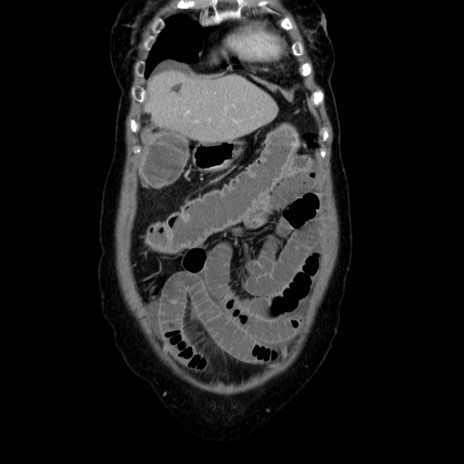

横断像

【症例】70歳代女性

【主訴】お腹が張る

【現病歴】1週間くらい前から腹部膨満の自覚あり。昨日夜から増悪したため、本日救急外来受診。

【身体所見】意識清明、BT 36.5℃、BP 165/106mmHg、HR 80bpm、SpO2 98%、腹部:膨満、軟、自発痛・圧痛なし、触診にて不快感あり、腸蠕動音:減弱

【データ】WBC 12600、CRP 1.04